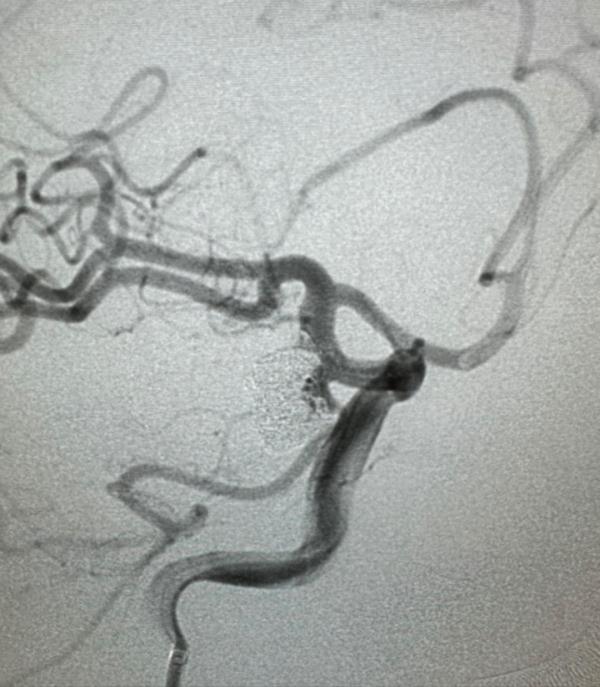

CT检查结果显示,姚江头颅右侧鞍旁明显结节状突起,蛛网膜下腔少许高密度影。进一步行头颅CTA检查,提示其右侧颈内动脉C7段后交通动脉起始处动脉瘤,左侧大脑中M1段动脉瘤。

术中,三位专家默契配合,首先在动脉瘤内放置了成蓝弹簧圈,再更加精细地在微导丝和支架导管互相配合下,将微导丝超选入后交通动脉,跟进支架导管,将开环支架头端定位在后交通动脉,近端定位在颈内动脉近端,瘤腔内填塞弹簧圈。最后造影,动脉瘤不显影、后交通动脉保留通畅,说明姚江颅内右侧的这一颗“炸弹”被顺利“拆除”。